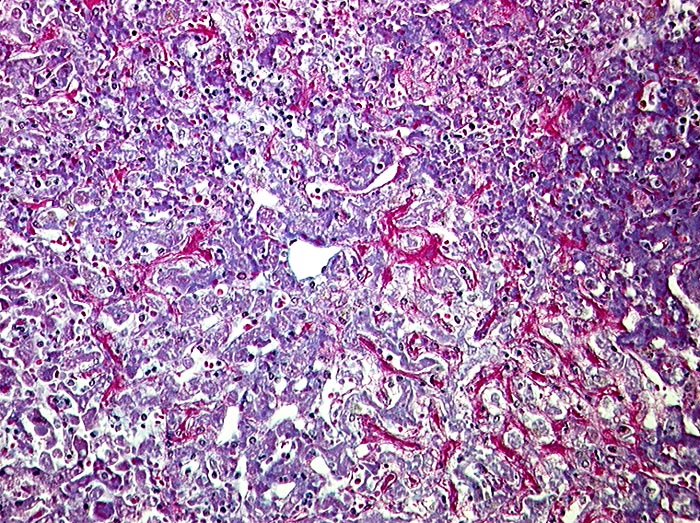

PathoPic – image database / PathoPic ID 1274 - Subakute Stauung

Subakute Stauung

vaskulär / Durchblutungsstörung

Leber

Znetralvene in der Mitte des Bildes. Die perivenulären Sinusoide sind prall gefüllt mit Blut. Die Leberzellbalken sind leicht verdünnt (druckatroph). Keine Fibrose.